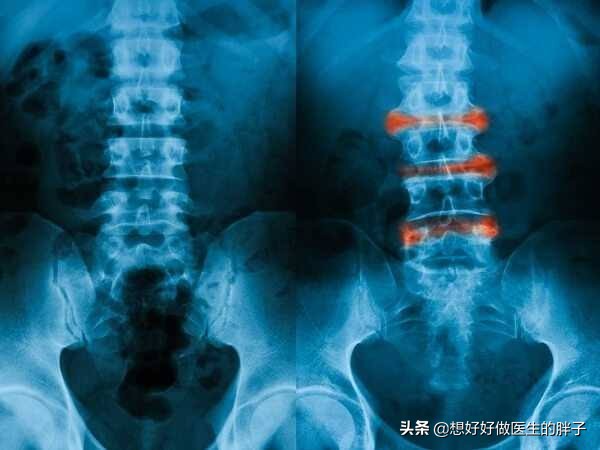

强直性脊柱炎属于风湿免疫科的疾病,具体的原因到现在也不是非常的明确,这种疾病主要累及骶髂关节、脊柱以及一些大的关节,病变的部位会发生比较严重的纤维化、骨化,患者出现疼痛以及日渐加重的活动受限。

其实这个疾病说起来还是非常复杂的,作为非医务工作者,大家可以把这个疾病理解为因为某些不明的原因导致本来是分成多个节段的脊柱或者是其它关节逐渐凝在了一起,就像有一个贼拿着一桶胶水在不停的涂抹患者的脊柱、骶髂关节,这样导致整个关节发生严重的粘连。

这个疾病最终在骨关节方面会导致整个脊柱(包括颈椎)严重的活动受限以及疼痛。很多患者的脊柱被逐渐的凝在了一起,而且会发生比较大范围的骨化,患者的脊柱由分节段的情况变成了类似竹节样融合在一起的状态,这是非常经典的一种强直性脊柱炎改变,我们称之为称之为竹节样改变。大家可以想一想,本来灵活多变的一个脊柱被逐渐凝在了一起,以后是否会发生活动的受限?是否会疼痛?

强直性脊柱炎中、晚期脊柱活动受限,检查x线可以发现典型的竹节样改变,诊断往往不难,早期诊断却容易和腰疼混淆,导致遗漏,早期的强直性脊柱炎患者以下的一些特点:

●脊柱x线检查,如果通过x线检查,能够看到明显的脊柱竹节样改变,可以作为诊断条件之一。